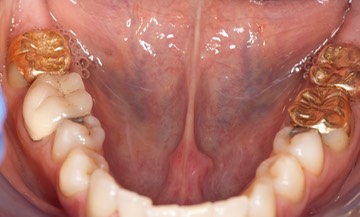

Photos of Clinical Operations

_DSC6212